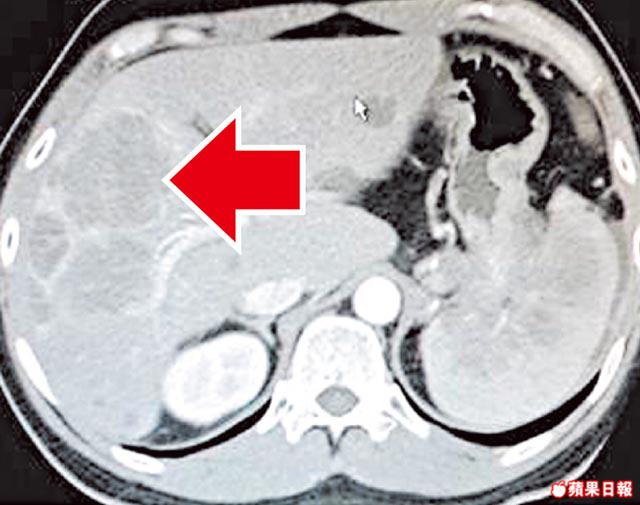

瑪麗醫院內科腫瘤科醫生梁澄宇表示,NET成因不明,可潛伏三至六年才有病徵。但年初有一名21歲少女確診,她持續肚痛兩至三個月,經電腦掃描後發現肝臟有兩個擴散性腫瘤,手術切除後發現是NET,「但未搵到原位神經內分泌腫瘤」,現正接受觀察,暫未知是否出現擴散。

梁續稱,如發現上述病徵,可透過電腦掃描、體抑素受體閃爍攝影、正子電腦斷層掃描等,檢查是否患有NET,找出其位置及觀察是否已擴散;並可透過手術或藥物進行治療。